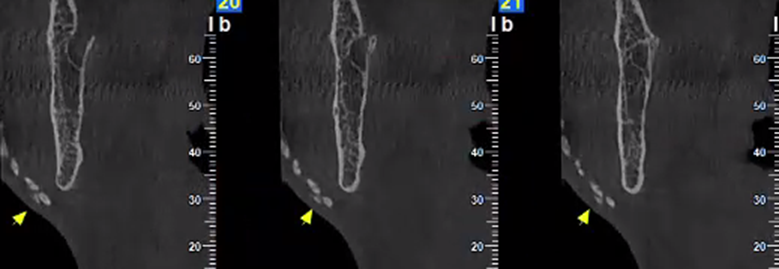

Εκτός από τις παραπάνω ελάχιστα επεμβατικές τεχνικές, στις απεικονίσεις της τραχηλοπροσωπικής χώρας μπορεί να συναντήσουμε και τα αποτελέσματα πιο επεμβατικών τεχνικών, όπως διάφορες μορφές πλαστικής χειρουργικής με χρήση ενθεμάτων σιλικόνης.

Ένα παράδειγμα είναι η γενειοπλαστική, όπως φαίνεται στην παρακάτω περίπτωση.